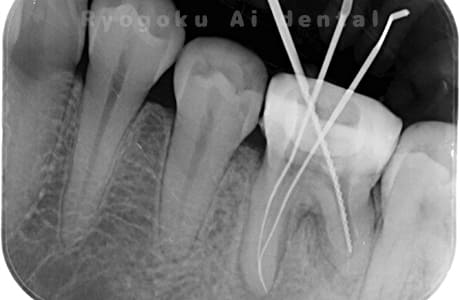

Case03

-

- 原因

- 急性化膿性根尖性歯周炎

- 治療期間

- 2ヶ月

- 治療内容

- マイクロエンド

- 治療費用

- 121,000円

黙っていても痛みが出るとのことで来院した患者様です。本治療は症状もあるため、抜髄治療をマイクロエンドで行いました。